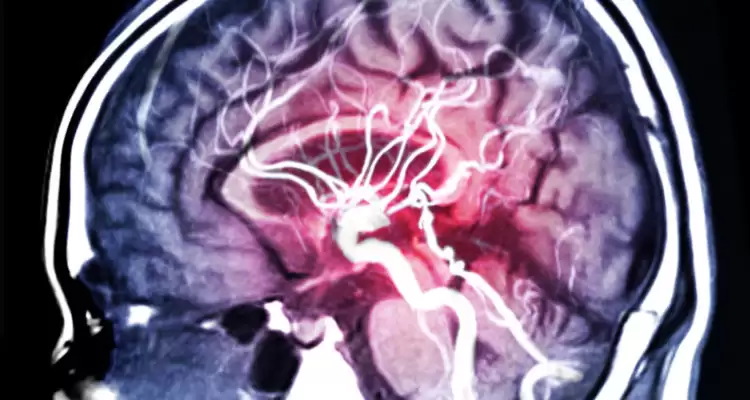

Інсульт виникає, коли мозок не отримує достатньо крові, що позбавляє його кисню і поживних речовин. В результаті клітини мозку відмирають. При цьому дослідження показують, що шанс зіткнутися з інсультом на 80% вище в один і той же час доби.